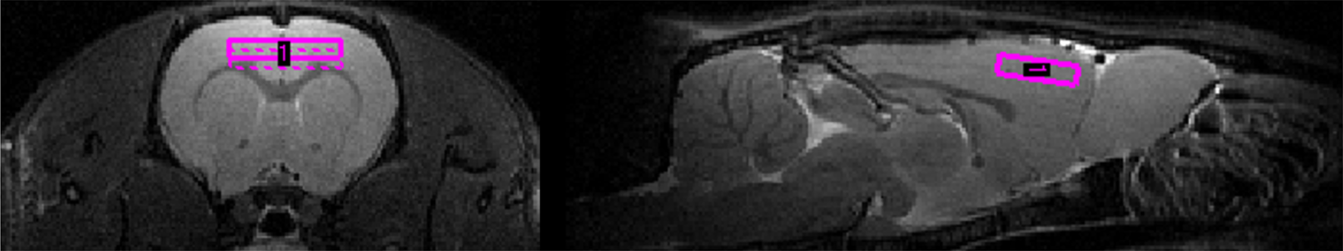

Figure 4

Voxel localization in the prefrontal cortex.